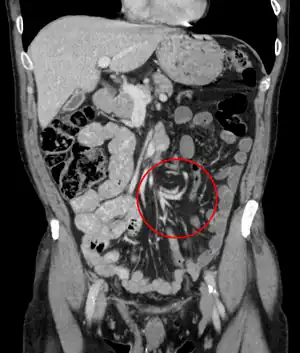

CT scan of a small bowel volvulus. It shows two juxtaposed segments of narrowing, which is the spot of mesentery rotation. The other signs indicate strangulation. -

CT scan of a cecal volvulus